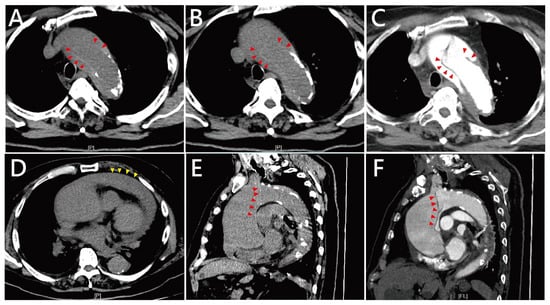

2. Case Presentation